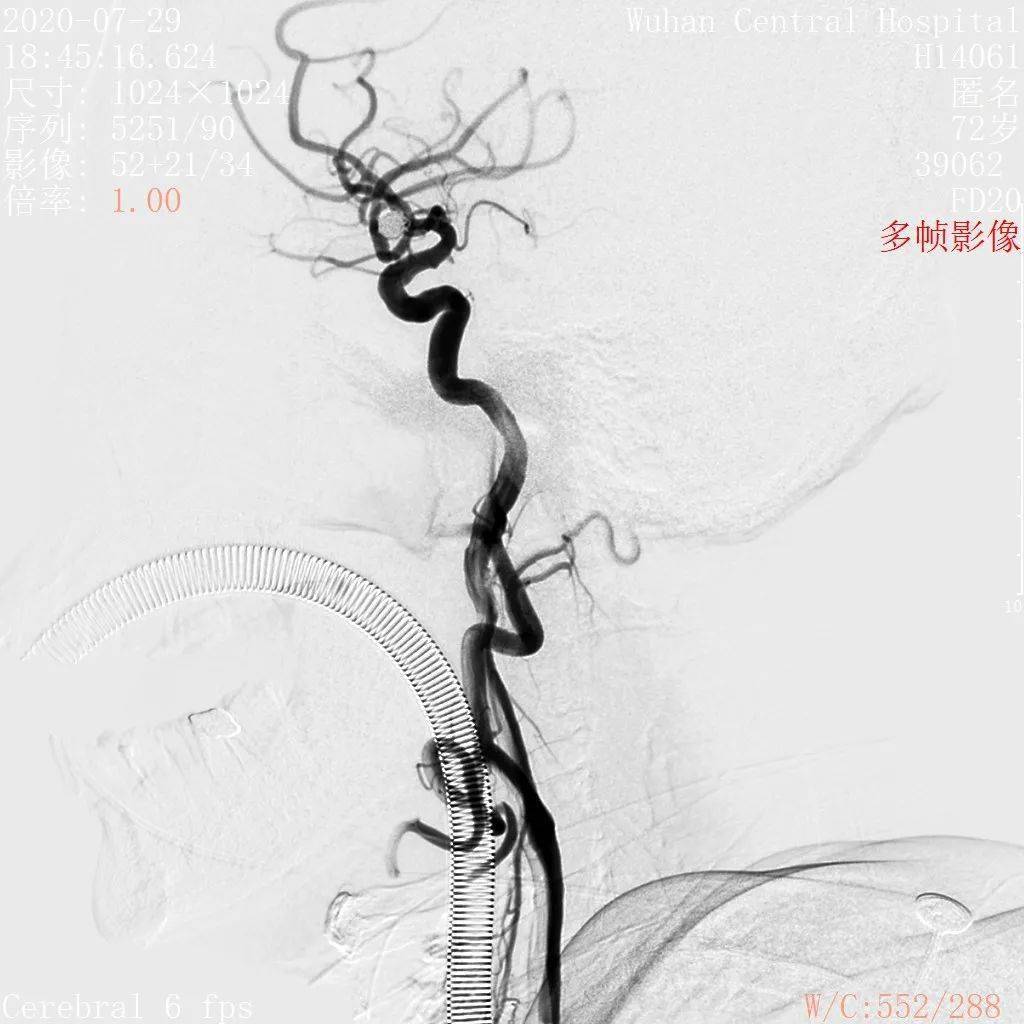

neuroform atlas支架治疗颅内动脉瘤

atlas支架结合双微导管辅助弹簧圈栓塞宽颈动脉瘤2例